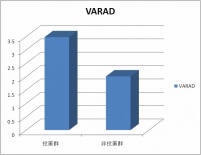

当院でのVSRAD データ

当院のデータでも、認知症がみられる方がVSRADの数値が高い値を示しているようです。

約100人ずつのデータです。